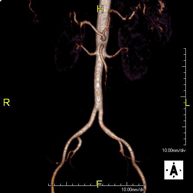

- Angio-RM Aorta abdominal

Prueba diagnóstica no invasiva que consiste en el estudio de la arteria aorta abdominal, obteniendo imágenes de alta definición anatómica mediante el empleo de un campo electromagnético y ondas de radio (con un emisor y un receptor). Es indispensable el uso de contraste paramagnético (Gadolinio). Sin embargo, no utiliza radiación ionizante. La calidad de las imágenes permite realizar reconstrucciones en 2D y 3D. Está indicado en aquellos pacientes con enfermedad vascular (aterosclerosis), estudio de aneurismas, en estudios pre-quirúrgicos de lesiones adyacentes a la aorta abdominal como "mapa" vascular, etc.

Prueba diagnóstica no invasiva que consiste en el estudio de la arteria aorta abdominal, obteniendo imágenes de alta definición anatómica mediante el empleo de un campo electromagnético y ondas de radio (con un emisor y un receptor). Es indispensable el uso de contraste intravenoso paramagnético (gadolinio). Sin embargo, no utiliza radiación ionizante. La calidad de las imágenes permite realizar reconstrucciones en 2D y 3D. Está indicado en aquellos pacientes con enfermedad vascular (aterosclerosis), estudio de aneurismas, en estudios pre-quirúrgicos de lesiones adyacentes a la aorta abdominal como "mapa" vascular…